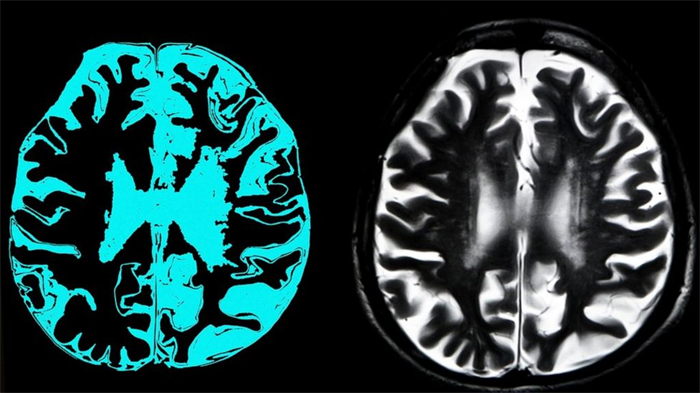

Andersen 补充说,Aducanumab 要么会引起对阿尔茨海默氏症项目更多注意力和更高评价,要么会削弱基于清除淀粉样斑块疗法的热情:“无论怎样,我们都希望继续投资于其他作用机制,尤其是 tau,以及其他能更好穿越血脑屏障的治疗手段,例如 Denali 的富含亮氨酸重复激酶 2 的小分子抑制剂(由 Biogen 授权),或是基于 RNA 的疗法。”